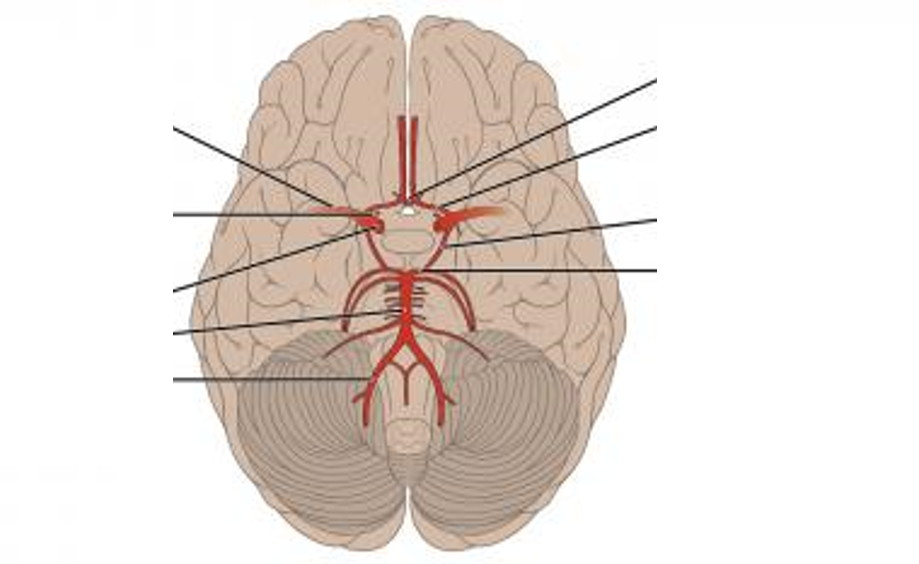

Label each of the arteries 1-9 (starting from top right and working anti-clockwise)

1 - middle cerebral 2 - ophthalmic 3 - internal carotid 4 - basilar 5 - vertebral 6 - posterior cerebral 7 - posterior communicating 8 - anterior cerebral 9 - anterior communicating